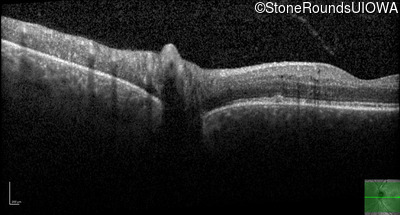

Optical Coherence Tomography - Right - 20/25 -1

Exemplar / OCT Stack